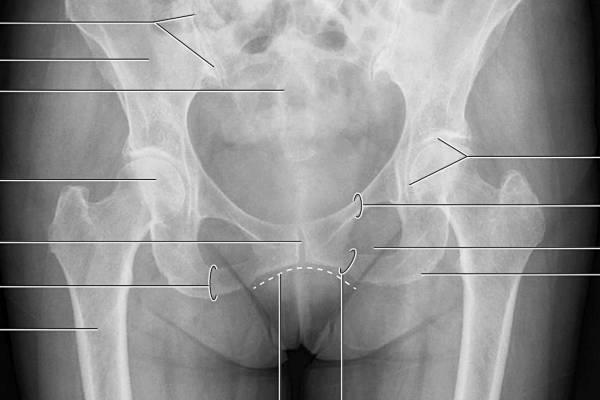

Диагностика мышечно-скелетной боли призвана исключить факторы риска, которые без адекватного лечения приводят к инвалидности: компрессионно-вертебральный (позвоночный, корешковый) синдром, спинальную патологию и факторы, вызывающие воспаление. В первую очередь необходимо провести обследование, выявить источник боли и подтвердить диагноз.

При первичной диагностике МФБС пальпацией выявляются триггерные точки. Далее диагноз миофасциального синдрома подтверждается такими инструментальными исследованиями, как УЗИ, термография мышц пояснично-крестцового отдела и электромиография (ЭМГ).